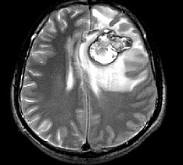

问题 男,34岁,3个月前行左额叶脑肿瘤切除术,近1个月又感头痛无恶心呕吐,近1周来又觉双下肢无力,并失语,请根据所提供图像,选择最可能的诊断()

选项 A.(左额叶)星形细胞Ⅱ级伴出血坏死(复发性) B.(左额叶)脑出血 C.(左额叶)海绵状血管瘤 D.(左额叶)动静脉血管畸形 E.(左额叶)脑肿瘤术后

答案 A